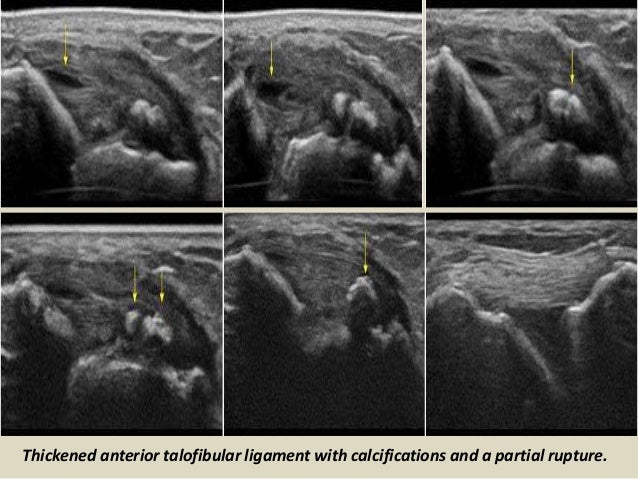

Thickened anterior talofibular ligament with calcifications and a partial rupture.

65. 65. Thickened anterior talofibular ligament with calcifications and a partial rupture.